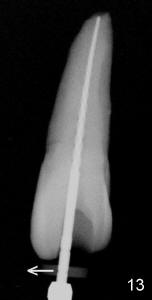

The tooth #8 of a 61-year-old man has obliterated canal probably due to trauma (Fig.1,2 (lateral view)). Initial access shows that the labial portion of the recessed pulpal horn (brown, < in Fig.3 (occlusal view) is not fully exposed, while that the most lingual aspect of the incisal edge (between **) has been removed. Further access appears to be necessary to expose the obliterated pulpal chamber (Fig.7 <) and more of the incisal edge has been violated ( between **). With good exposure, the canal is easily found around the arrowhead (<) in Fig.7. Laterally, the initial file: C6 is straight and slightly labial to the incisal edge (Fig.6). But it is somewhat bent in the front view (Fig.5). After enlargement of the coronal canal with Gates-Glidden files #2 and 3 (Fig.9<), #20 file appears to move distally (<-) and is straighter than the file in Fig.5. Laterally, the #20 file remains without much tension and around the incisal edge (Fig.10). Fig.11 shows occlusal view of the access after application of Gates-Glidden files. Before rotary files, the access is enlarged further both labially and lingually with diamond/carbide endo access burs (Fig.15). Fig.13,14 show 40/.04 file in the canal free without strain. The file seems to move distally further (Fig.13 <-).